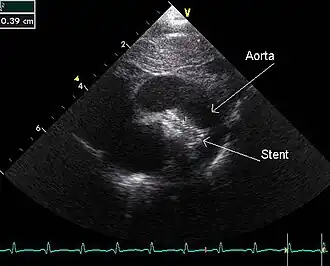

Stent

Een stent is een metalen of kunststof buisje dat in medische toepassingen in een vat of kanaal in het lichaam van een patiënt wordt geplaatst, bijvoorbeeld in een bloedvat, met het doel om dit kanaal open te houden.

Het belangrijkste doel van een stent is het corrigeren van vernauwingen in de doorsnede van vaten en kanalen in het lichaam. Zo worden stents vaak gebruikt om drukverschillen in de bloedstroom te verminderen in het geval van gedeeltelijke blokkering en zodoende een voldoende toevoer van bloed naar organen te verkrijgen. Hoewel stents meestal gebruikt worden voor de kransslagaders, worden ze ook voor andere kanalen in het lichaam gebruikt, zoals andere slagaders, de slokdarm, luchtpijpen en urethra.